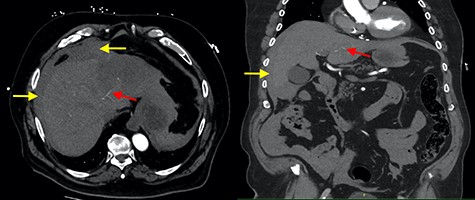

He was hypotensive (systolic 60 mmHg) with a grossly distended abdomen that was tender to palpation in all quadrants with associated guarding and localized peritonism in the right upper quadrant. A bedside ultrasound of the abdomen suggested a peri-hepatic collection. After initial resuscitation, haemodynamics improved and the decision was made to perform a computer tomography (CT) angiogram to identify a bleeding source. This confirmed a peri-hepatic collection predominantly located around the left lobe of the liver with contrast extravasation from a prominent vessel extending towards the liver capsule (Fig. 1). Resuscitation continued with the activation of a massive transfusion protocol. Prothrombin concentrate and tranexamic acid were administered to partially reverse rivaroxaban, after coagulation studies revealed an international normalized ratio (INR) of 6.7. A Child-Pugh score of 9 (Class B) was calculated, placing the patient at a 30% risk of peri-operative mortality.

Axial and coronal contrast images of abdomen (yellow arrow—haemoperitoneum, red arrow—contrast extravasation from segment II/III artery).